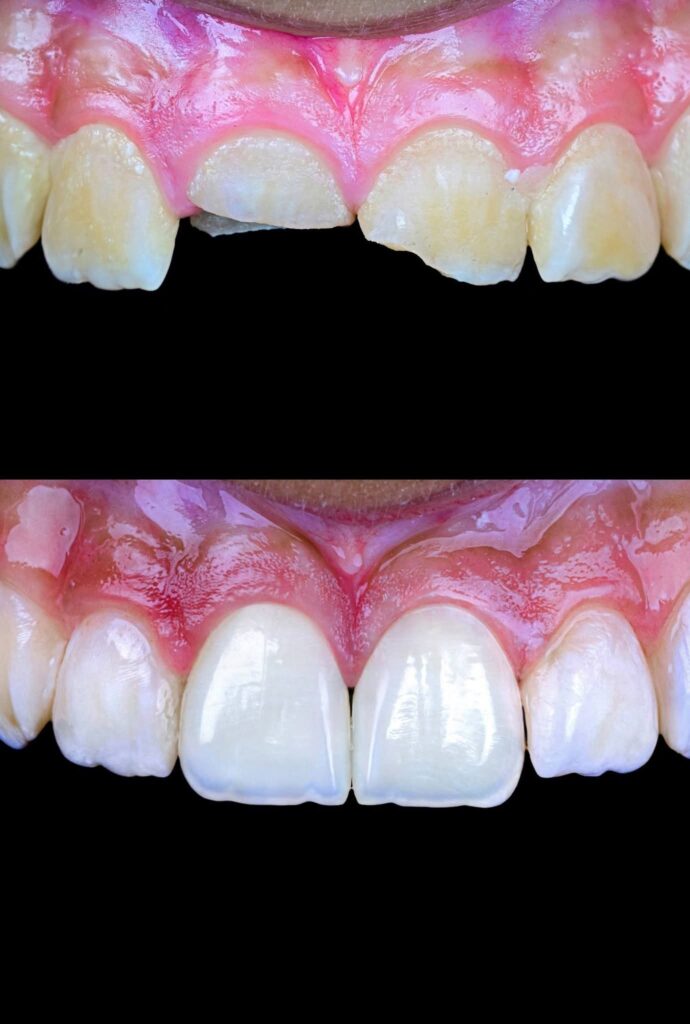

Symmetry and proportionality are fundamental principles in aesthetic dentistry, particularly in direct composite veneers, where the clinician acts simultaneously as a scientist and an artist. Successful veneers are not determined only by color and shape, but by the harmony between teeth, gingiva, lips, and face.

Symmetry refers to the mirror relationship between the right and left sides, especially the maxillary central incisors. Absolute symmetry is not always natural; therefore, perceived symmetry is more important than mathematical symmetry. Small differences in line angles, embrasures, and incisal edges can be used intentionally to create a natural appearance.

Direct composite veneers require a balance between mathematical proportions and artistic perception. The most aesthetic result is achieved not by perfect symmetry, but by natural, harmonious asymmetry combined with correct proportions.